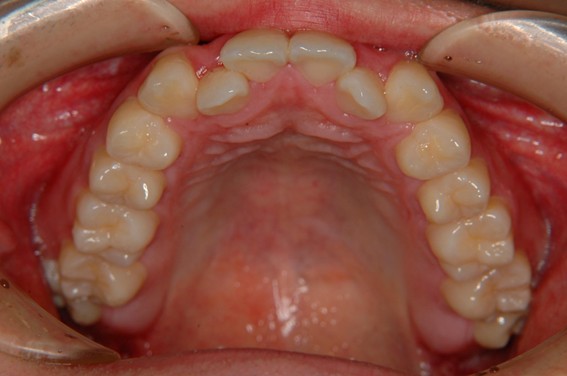

| 主訴 | 前歯が逆に噛んでいるところがある。歯のがたつき。 |

| 治療内容 | 表側ワイヤー矯正、4本抜歯を行いました。 |

| 治療費 | 880,000円+ダイレクトボンディング33,000円(税込) |

| 治療期間 | 30ヶ月 |

| 治療回数 | 30回 |

| 想定されたリスク | 歯根吸収、歯髄壊死、歯髄充血、歯肉退縮のリスクがありました。 |